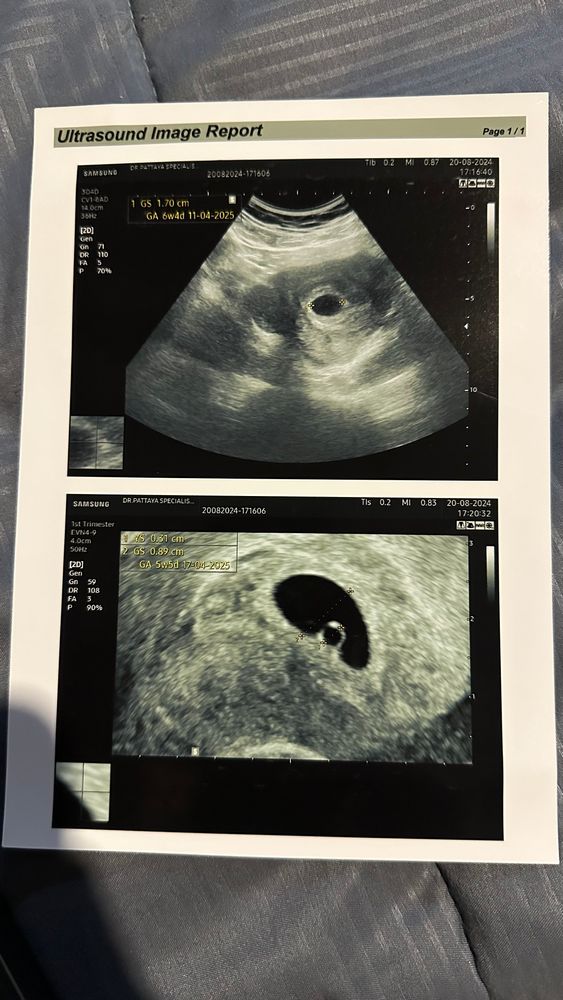

Нет эмбриона( посмотрите пожалуйста

Ксюня, так обычно называют эмбрион на раннем сроке беременности. Эмбрион бриллиант, а желточный мешочек само колечко)) а все вместе выглядит как колечко с бриллиантом))) Изображение

В 6 недель 2 дня только увидели. Хотя почти в 6 еще не было. ЖМ очень хорошо что есть, большая,вероятность, что появиться эмбриончик.

У меня была поздняя овуляция.В 6+2 акушерских недель было пустое пя 10 мм,без жм даже,эмбриона не было.Через неделю в 7+2 срок появился и жм,и эмбрион был почти 5 мм,и сб было.Через неделю повторите УЗИ.

И да,автор,пожалейте вены,хгч сдавать уже нет смысла,хгч может и удваиваться и расти хорошо,потому что будет расти пя,а эмбрион может так и не появиться.Тут только отслеживать динамику по УЗИ.Подождите неделю спокойно и тогда уже станет всё понятно.Жм есть у вас - это уже хороший знак.

Если есть ЖМ, то, скорее всего, будет и эмбрион. Отсутствие эмбриона при ЖМ - большая редкость

Один в один вами по сроку и тоже сегодня на УЗИ не увидели эмбрион. Яйцо 12 мм жм 3.5 Надеюсь на лучшее

Ксюня, у меня при хгч 12800 нашли только ПЯ и ЖМ. Переделала узи через 5 дней - был эмбрион и сб. Какой размер ПЯ у вас?

Валентина Н, ПЯ 17мм я так поняла

Ксюня, до ПЯ 25 эмбрион еще может появится. Переделайте узи через дней 5.